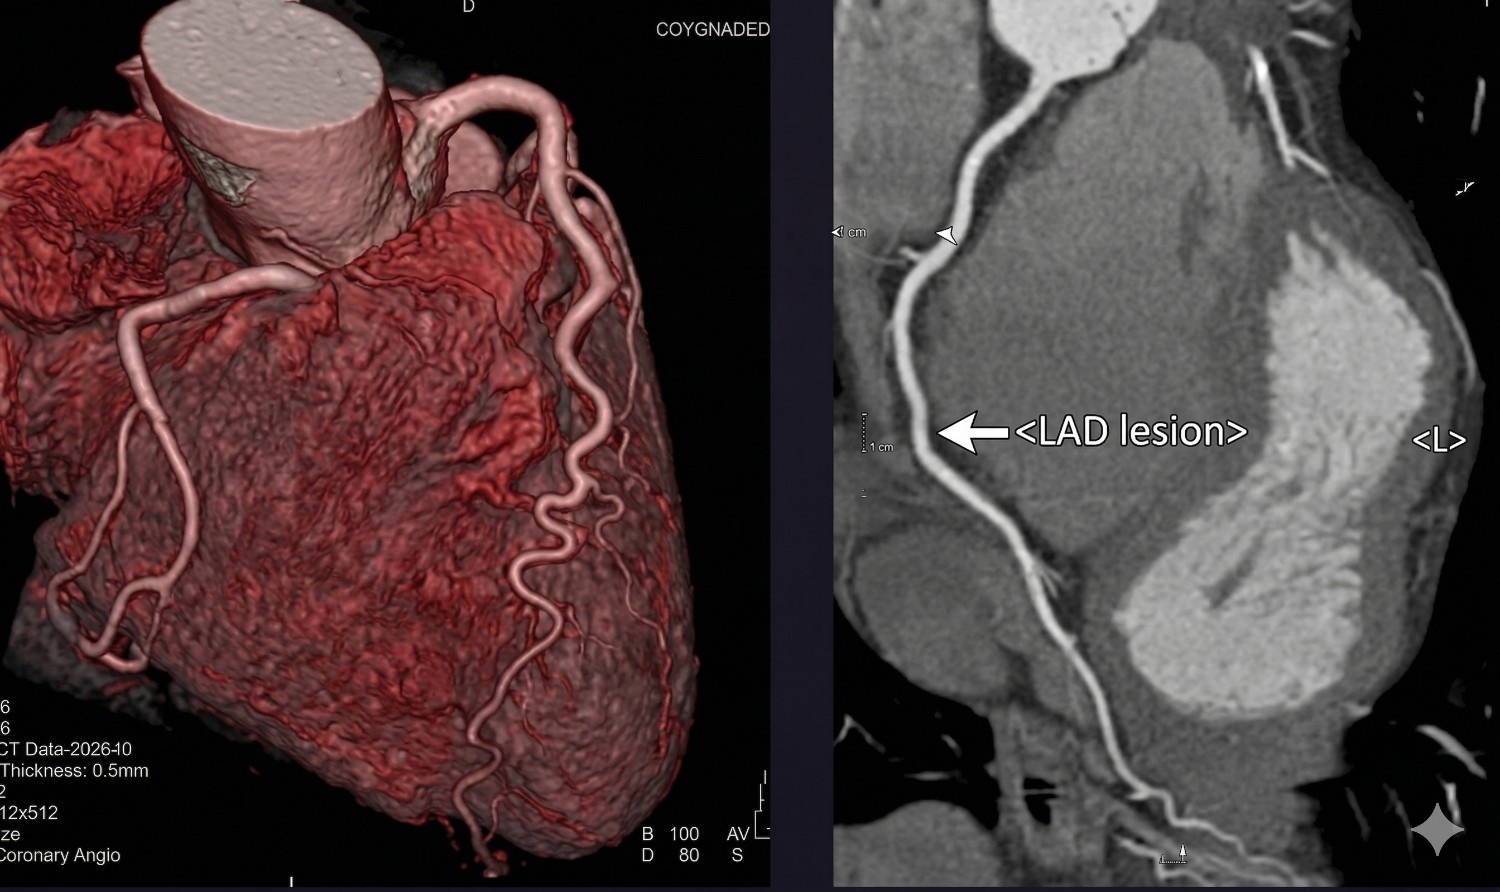

CT Scans

Multi-phase computed tomography reporting across all body systems — trauma, oncology staging, vascular, and emergency protocols. Structured reports with subspecialty correlation and clinical recommendations delivered with industry-leading speed.

Head & Neck Chest Abdomen/Pelvis Spine Angio-CT Trauma